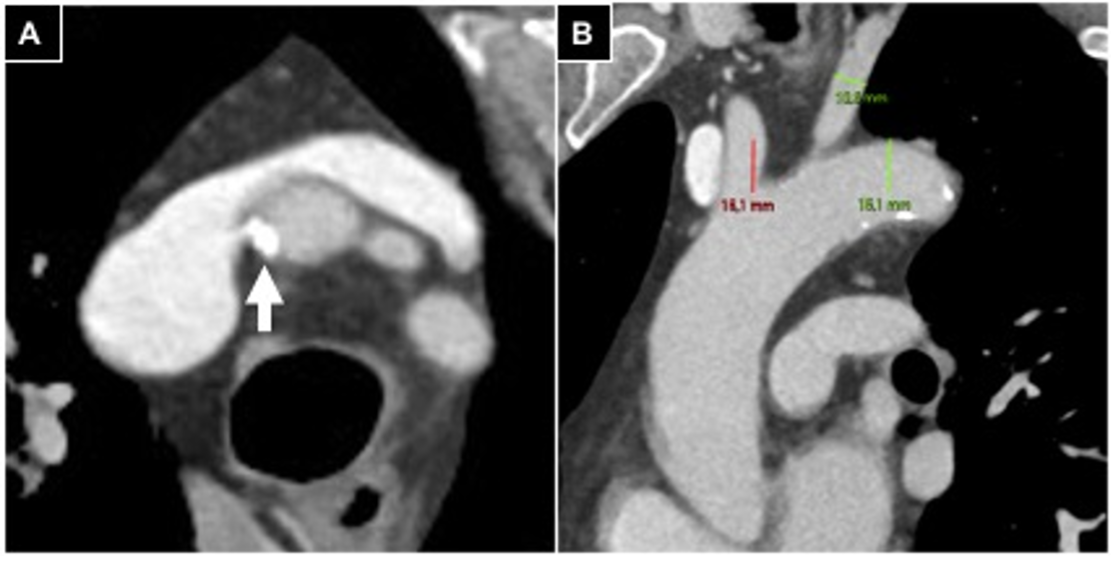

2.2. Pre-Procedural Clinical Evaluation

2.3. Pre-Procedural Vascular Evaluation

- Iezzi, R.; Posa, A.; Contegiacomo, A.; Maresca, A.; Rodolfino, E.; Merlino, B.; Bilhim, T.; Guimaraes, M. Application and Validation of a transRADial Access Score (RAD-Access) in Patient Selection for Safe Radial Access in Liver Cancer Intra-Arterial Procedures. Cancers 2025, 17, 1385. [Google Scholar] [CrossRef]